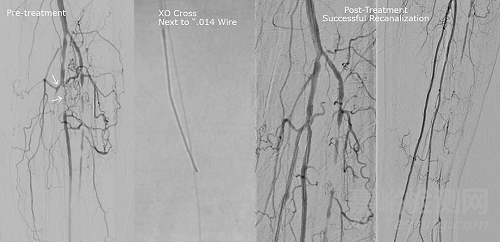

膝下慢性完全閉塞,多部位介入 圖片來源:Transit Scientific官網(wǎng)